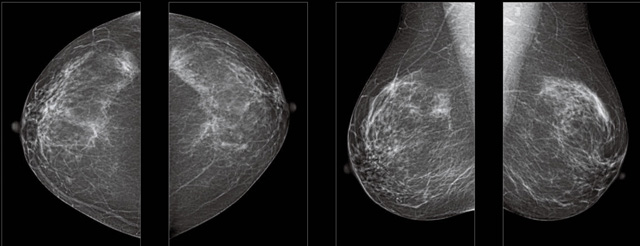

首先不同年齡階段的乳腺篩查頻次種類不一樣。青春期女性第二性征明顯發育開始,每個月進行自我乳腺檢查。20-30歲的女性就不推薦進行乳腺檢查,因為年輕女性的乳腺組織非常緊急。鉬靶X光線等檢查的射線不能辨別腫塊跟腺體。身體就白吸收了輻射,影響了身體健康。每個月自檢一次就是在洗澡時候,對著鏡子看看乳房外觀正常,皮膚潰爛、腫塊、顏色改變、再摸一下有沒小疙瘩。乳腺高危人群,特別是有乳腺CA遺傳傾向的女性,乳腺導管跟小葉不典型增生,原位癌。30歲前有乳房放療的女性。乳腺癌篩查可以把年齡提前到40歲前。40到70歲的女性可以在適合的機會篩查。

采用影像檢查技術來發現疑似特定病檢查跟人群的普查。一到兩年進行一次X光線的乳腺檢查。記過是C或者D型,可以加上B超協同。還可以一年一次核磁共振MRI檢查。70歲以上的女性認為絕經的女性是比較安全的。實際上也有乳腺癌的風險。65歲以上風險也很大。也是需要進行機會性篩查。